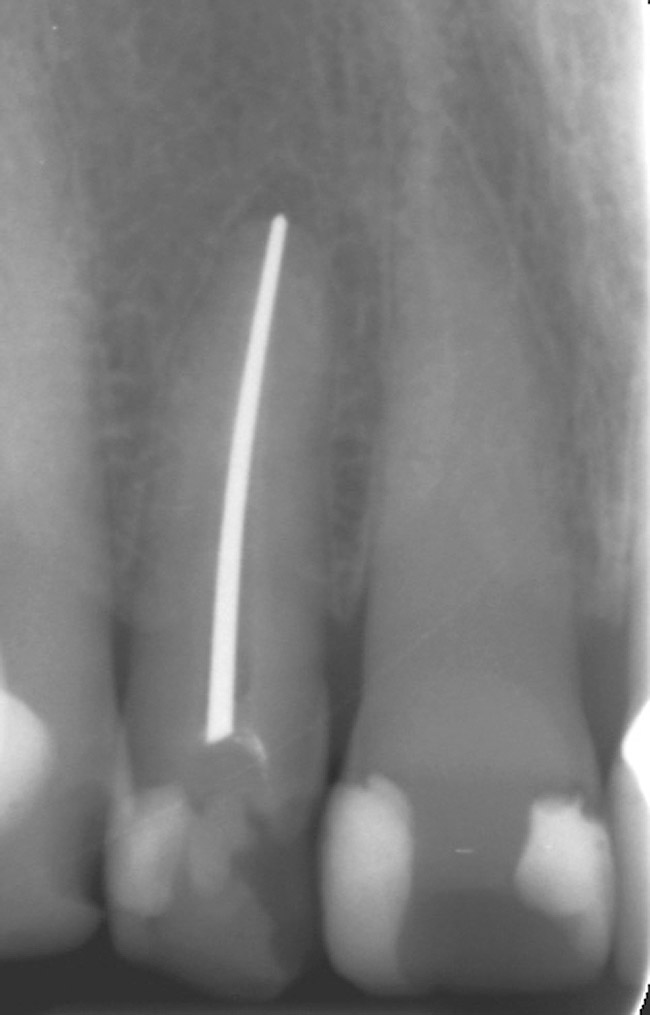

Figure 3  A radiograph will indicate whether the dark color is related to materials remaining in the pulp chamber, leaking restorations, caries, internal resorption, or failed endodontic therapy.

Figure 3

Figure 4  Endodontic therapy was attempted on a tooth with calcific metamorphosis, with subsequent perforation and file fracture in the PDL.

Figure 4